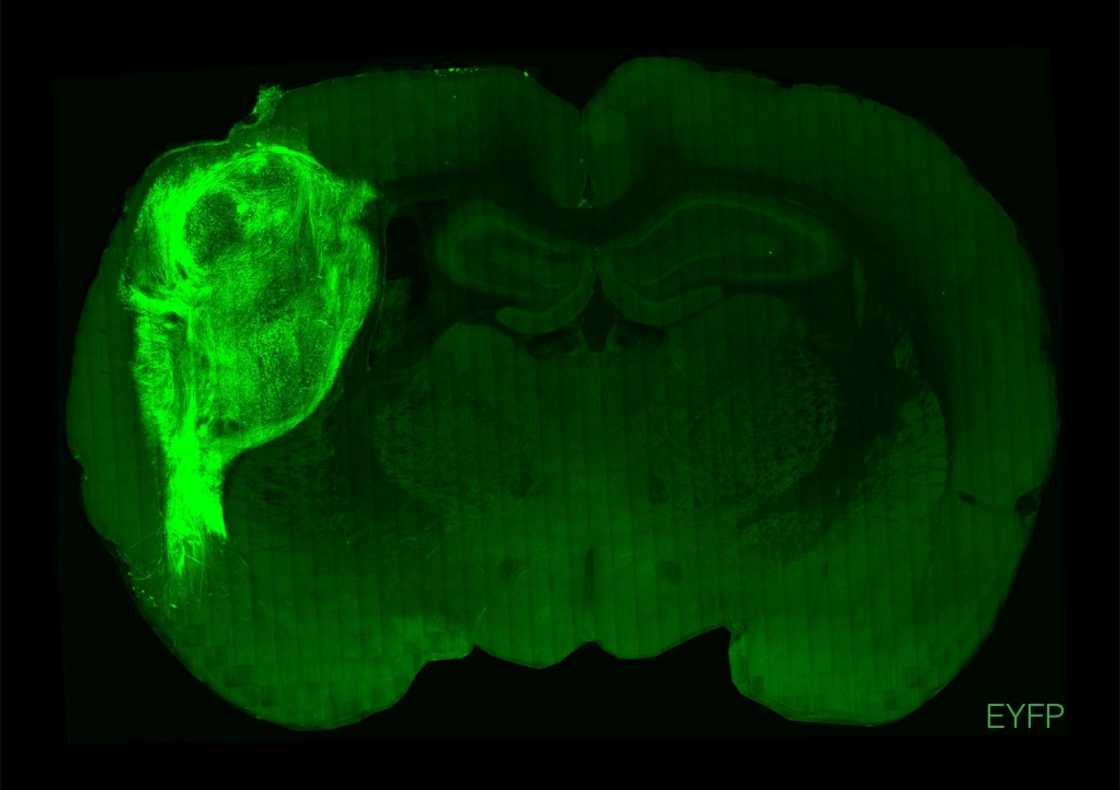

"By transplanting them at these early stages, we found that these organoids can grow relatively large, they become vascularised (receive nutrients) by the rat, and they can cover about a third of a rat's (brain) hemisphere," Pasca said.

To overcome those limitations, researchers implanted the groupings of human brain cells, called organoids, into the brains of young rats.